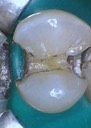

Joe Cha #20 prep